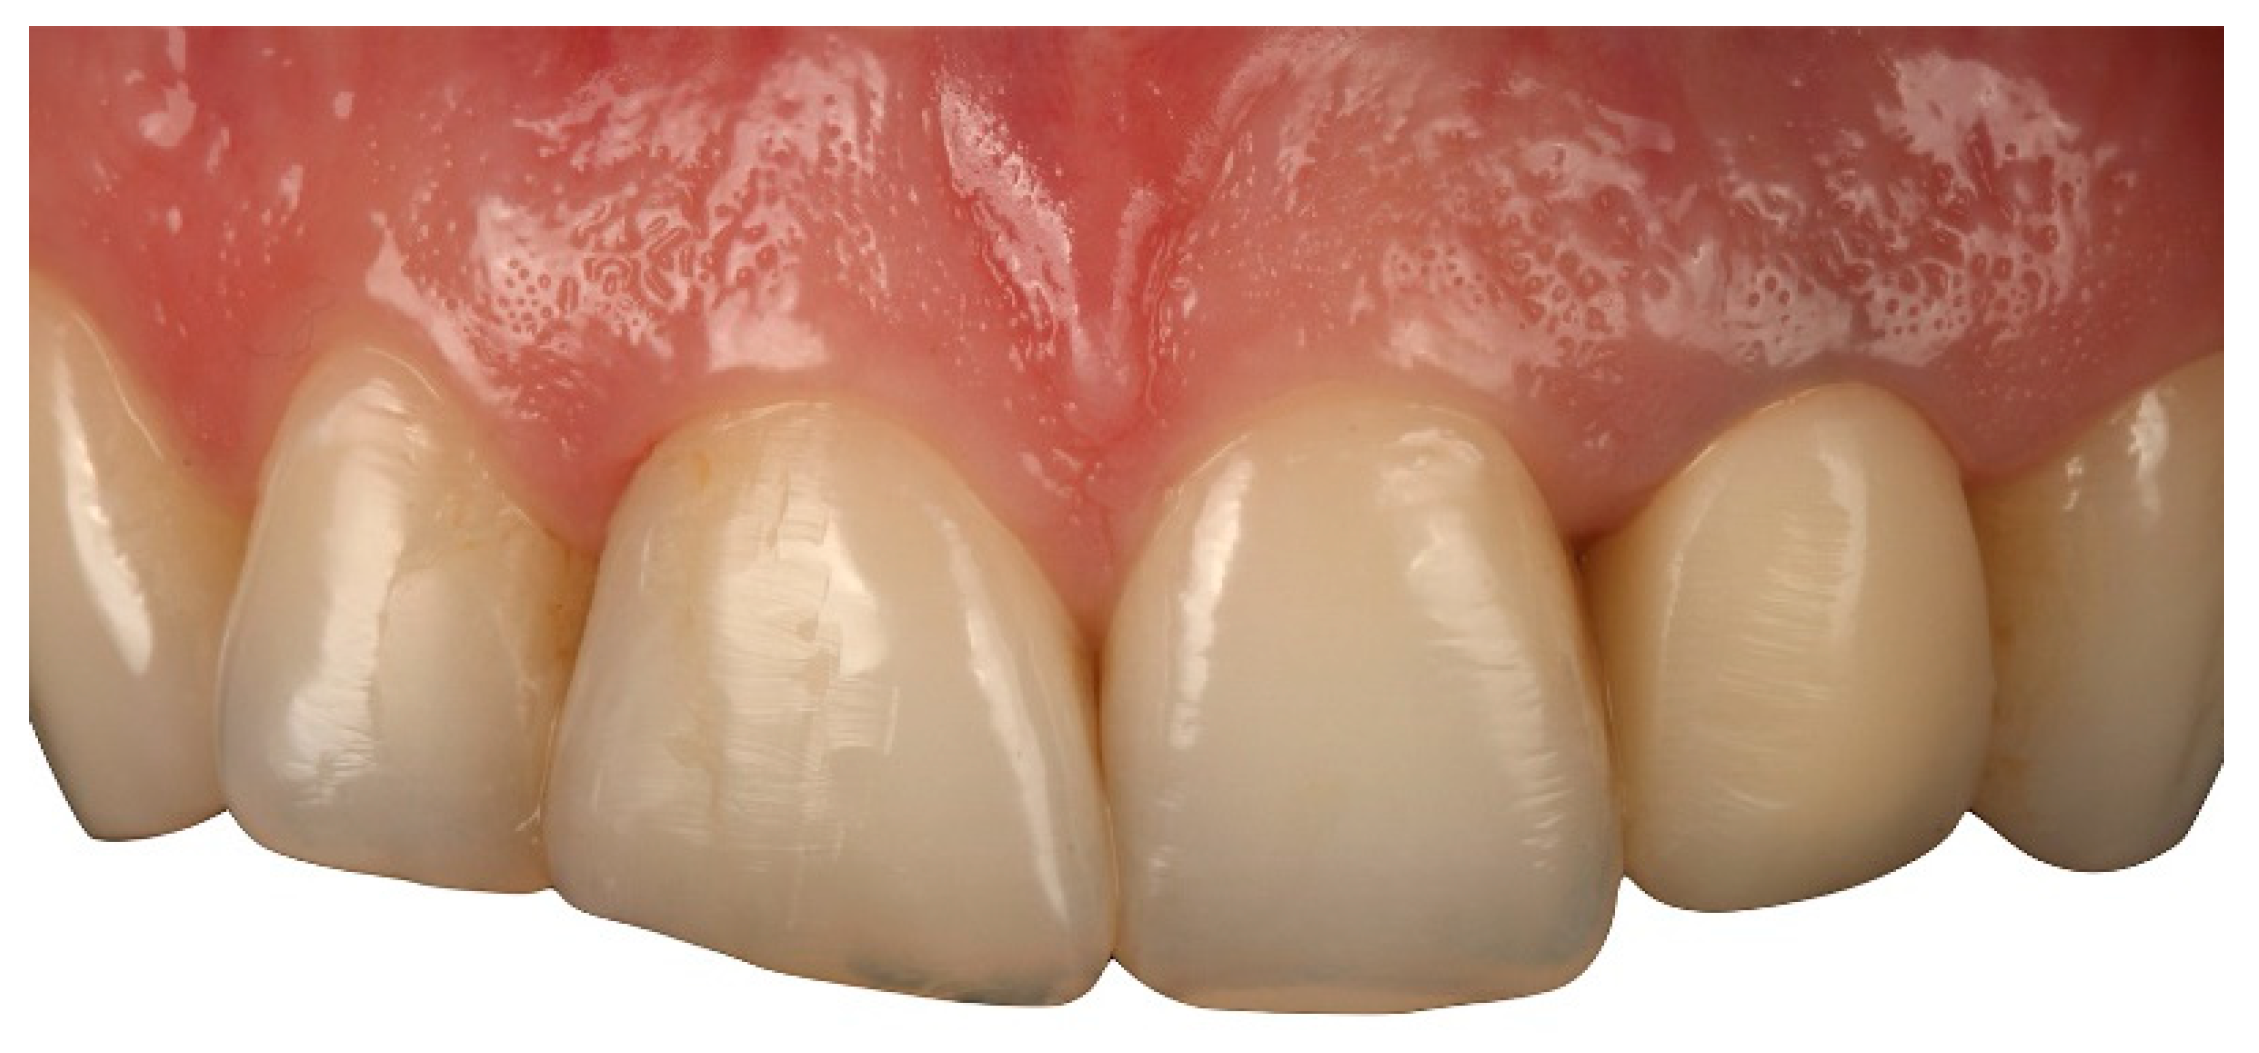

The clinical experience of BOPT reported in the literature has established that this technique increases the thickness of gingival tissue and enhances the stability of the soft tissue in the medium- and long-term compared to other classical preparations with finishing lines [5,7,8] (Figure 16, Figure 17, Figure 18, Figure 19 and Figure 20).

Figure 16. Retreatment of a fixed prosthesis with the BOPT technique. Initial pretreatment situation (Front view).

Applsci 10 04108 g016

Figure 17. Retreatment of a fixed prosthesis with the BOPT technique. Initial pretreatment situation (Lateral view).

Applsci 10 04108 g017

Figure 18. Gingiva after perioperative treatment with BOPT.

Applsci 10 04108 g018

Figure 19. Situation after treatment with BOPT (Front view).

Applsci 10 04108 g019

Figure 20. Situation after treatment with BOPT (Lateral view).